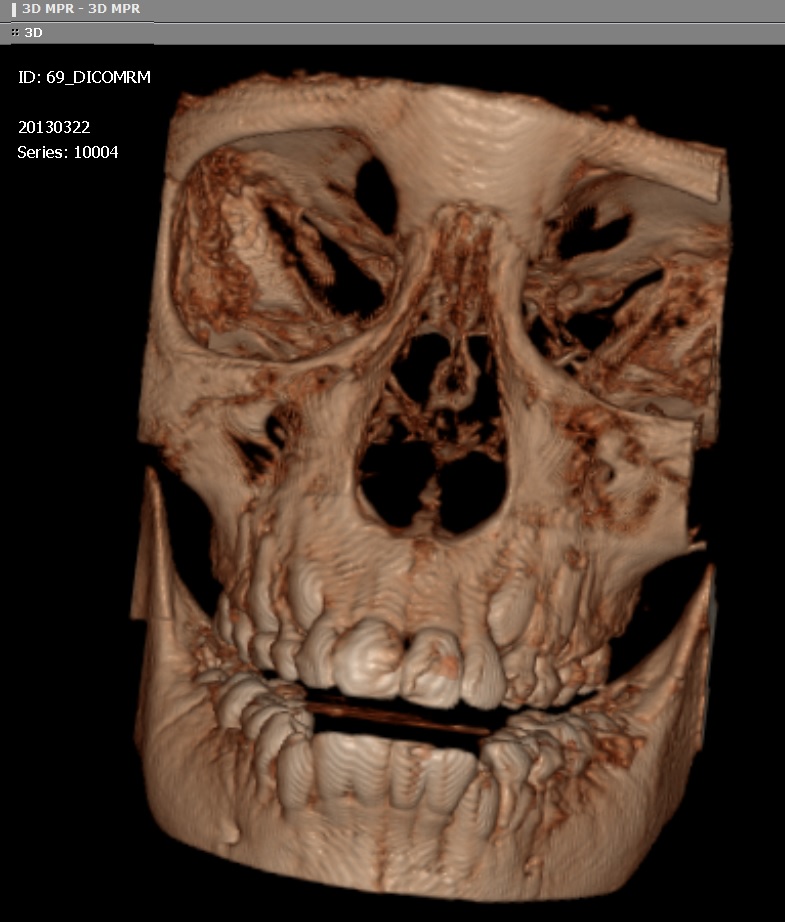

3. Realización de reconstrucciones multiplanares isotrópicas en diferentes planos estrictos, oblicuos, curvos o irregulares. Esto significa que se obtienen imágenes en los planos coronal y sagital de la misma calidad que los originales en el plano axial. También pueden realizarse reconstrucciones volumétricas, lo cual facilita la comprensión espacial de la patología, ayudando a la planificación terapéutica. Existen varias técnicas (por ej: MIP o máxima intensidad de proyección y MiniMIP o mínima intensidad de proyección; representación de volumen o “volume rendering” y representación de superficie o “surface rendering”) que el radiólogo puede utilizar para destacar elementos anatómicos o patológicos.

Para el estudio con equipos de tomografía computada helicoidal convencional de alta resolución del macizo facial (oídos, órbitas, senos paranasales, etc.) se requiere la realización de 2 adquisiciones: una en plano axial y otra en coronal. Las imágenes en plano coronal pueden verse degradadas por la presencia de amalgamas dentales, además de resultar dificultoso el cambio de decúbito en el caso de pacientes añosos o doloridos. Estos artificios e incomodidades pueden evitarse con la TAC al efectuar sólo una adquisición de cortes ultrafinos en el plano axial en pocos segundos y al realizar luego, en la estación de trabajo, las reconstrucciones coronales y sagitales u oblicuas, con excelente resolución, similar al plano de adquisición.